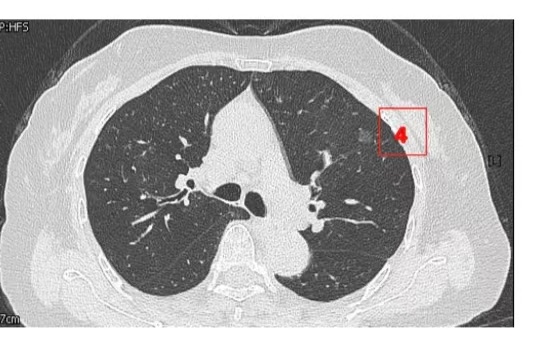

患者女性,71岁,因“发现左肺多发结节2周”入院。胸部CT提示左肺多发磨玻璃结节,较大者位于左肺上叶,呈类圆形,边界清晰,最大直径约9mm。该CT表现高度提示恶性可能。鉴于患者结节数量较多,为减少术中肺组织损伤,术前于CT引导下行经皮肺结节定位术,继而实施胸腔镜下左肺楔形切除术。术中共切除肺部结节6枚。术后病理示:左肺上叶较大结节(4号)为微浸润腺癌,其余5枚结节均为原位癌。患者术后恢复良好,于术后第1天拔除胸腔引流管,第4天顺利出院。

▲术前定位